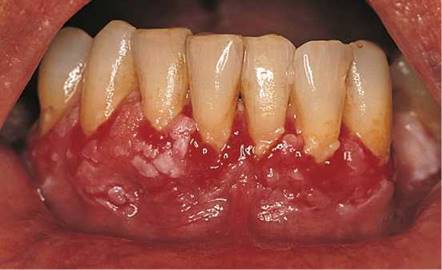

There are many causes of gingival hyperplasia, including heredity, hormonal imbalances of puberty and pregnancy, medications, and leukemia. Gingival hyperplasia is common in patients taking phenytoin (Dilantin), an antiepilepsy medication, and in those taking nifedipine, a calcium channel blocker. It has been estimated that gingival hyperplasia develops in 30% to 50% of all patients taking phenytoin. The hyperplastic gingival changes of hormonal imbalances usually recede once the hormones have returned to their normal, lower levels. Figure 12-21 depicts marked gingival hyperplasia in a patient who was taking phenytoin. Dense leukemic infiltration of the gingiva is commonly seen in acute monocytic and acute monomyelocytic leukemia. Figure 12-22 shows gingival enlargement and bleeding caused by acute monomyelocytic leukemic infiltration.

Figure 12-22 Gingival hypertrophy in a patient with acute monomyelocytic leukemia. Note the bleeding gingivae.